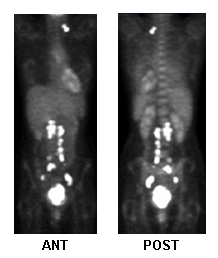

tomografía por emisión de positrones (TEP) de cuerpo entero

Prueba

Se utiliza para evaluar la propagación local/metastásica y ayudar en la planificación del tratamiento.[98][103]

Detección de recurrencia: sensibilidad 80%, especificidad 100%.[105][Figure caption and citation for the preceding image starts]: TEP con fluorodesoxiglucosa para la planificación del tratamiento, actividad metastásicaDe la colección de Neil S. Horowitz, MD; utilizado con permiso [Citation ends].

Resultado

puede mostrar una mayor actividad metabólica en las áreas afectadas